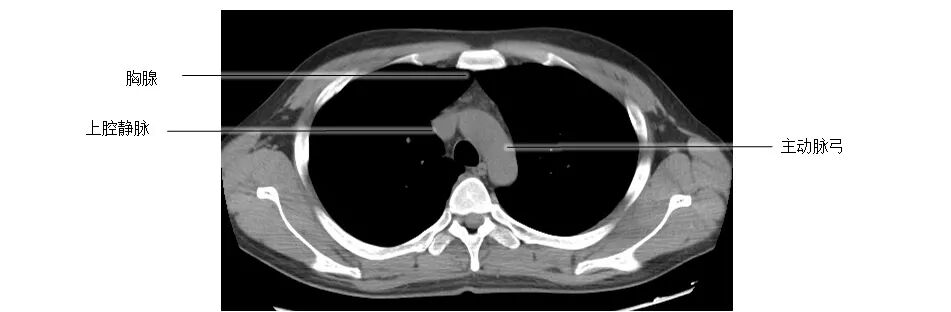

正常胸部CT影像是从横断面显示解剖和病变,可显示的结构包括胸廓、气管和支气管、肺、胸膜、纵隔和膈,CT的重建图像可从各个角度显示胸部解剖情况。不论采用何种图像显示方式,把握基本解剖结构都是必不可少的,一起学习胸部CT肺窗和纵隔窗的正常解剖。

胸部CT纵膈窗